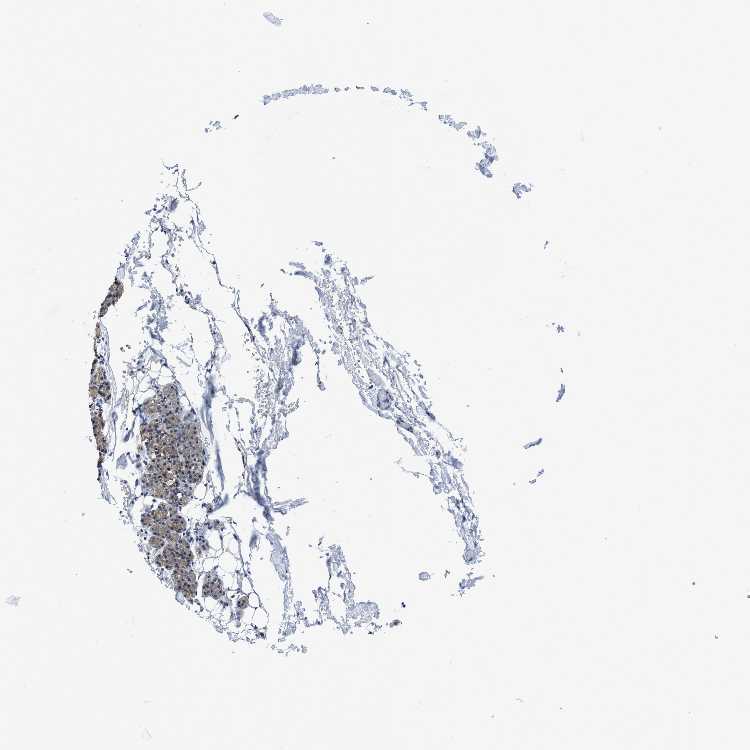

SALIVARY GLAND - Antibody stainingi

Antibody staining in the annotated cell types in the current human tissue is reported as not detected, low, medium, or high, based on conventional immunohistochemistry profiling in selected tissues. This score is based on the combination of the staining intensity and fraction of stained cells.

Each image is clickable and will lead to virtual microscopy that enables deeper exploration of all samples and also displays staining intensity scores, fraction scores and subcellular localization as well as patient and tissue information for each sample.

Antibody HPA008423

Glandular cells Medium